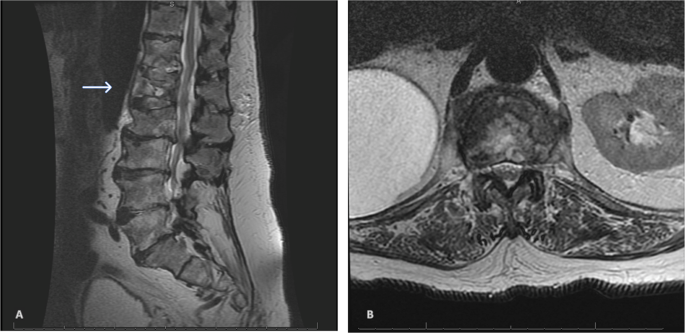

An 82-year-old male presented with a remote history of prior falls and a recent traumatic compression fracture of his L1 vertebral body. He reported no previous fractures, weight loss or antecedent pain. He was initially treated with a brace and underwent physical therapy. At follow-up, he had no neurological deficits but demonstrated severe recurrence of pain with progressive functional impairment refractory to conservative management. An MRI showed a worsening L1 vertebral body collapse, a T12 inferior endplate fracture, and a L2 superior endplate fracture (Fig. 1). The imaging was suspicious for a pathologic etiology. With his intractable pain and collapse at the thoracolumbar junction, we proceeded with a kyphoplasty of L1, vertebroplasty of T12, and obtained a bone biopsy for pathology and culture (Fig. 2). The initial smear testing for acid-fast bacilli (AFB) was negative with an interim negative report at 2 weeks, and final identification of M. abscessus at 6 weeks. The infectious disease (ID) service was consulted for further management. The smear was presumed to be a contaminant given his history and presentation.